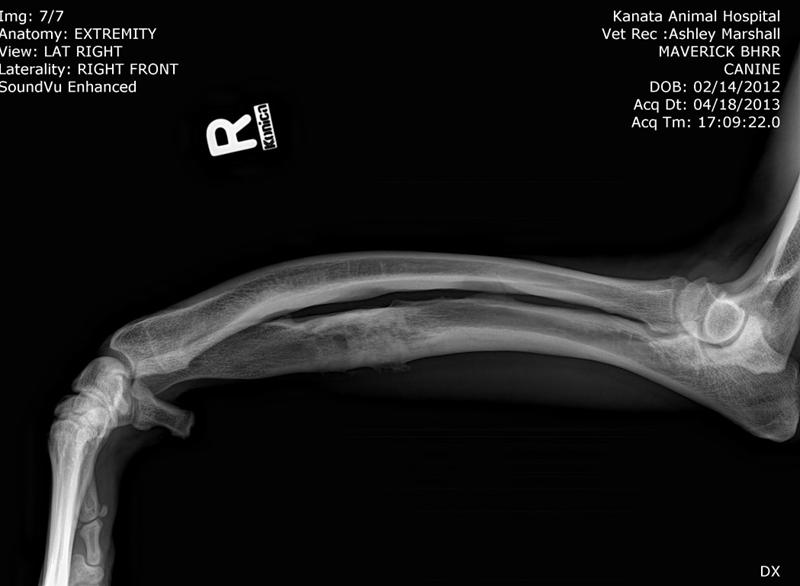

His surgery to remove the implant on his left front leg after a sudden rejection/infection with the plate screws was on September 24th. This is his fourth leg surgery. He had two surgeries on his front legs which were deformed when he first arrived to BHRR and then now he has had to have two more surgeries due to reacting to the Implants.

BHRR’s Mavie, for those who are not familiar with his journey has had two surgeries on his front legs, ended up reacting to the fixator on the left front leg, then last November rejected the implant in the right front leg and now, is having symptoms very similar on the left front leg.

As many are aware, in November of 2014, BHRR’s Maverick, had a violent aggressive reaction to the implant in his right front leg and had to spend several months on strong antibiotics, had to have an emergency surgery to remove the plate/screws and was treated for a terrible abscess from reacting to the implant. His ortho specialist even cultured the implant to see what may be brewing on it…..

How it started with his right leg is how his left leg is now ‘appearing’ to be.